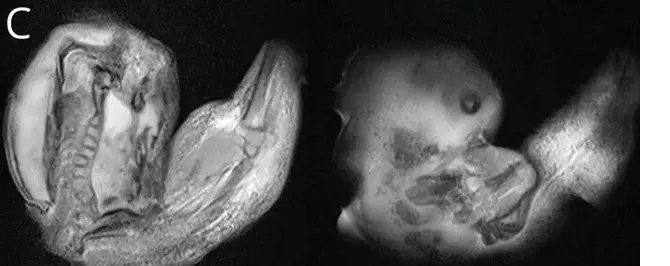

Amerikan Nöroloji Akademisi'nin 'Neurology' adlı tıp dergisinde yayınlanan bir makalede detayları paylaşılan bu olay, tıp camiasında büyük şaşkınlık yarattı. Bebeğin kafatası incelendiğinde, beyninin sıkıştığı ve sıvı birikimi oluştuğu belirlendi. Daha detaylı incelemeler, bebeğin aslında anne karnında bir ikiz kardeşi olduğunu ve bu ikizin yeterince gelişemeyerek bebeğin kafatasının içine sıkıştığı ortaya çıktı.

Doktorlar, fetüsün üst uzuvlarının, kemiklerinin ve hatta tırnaklarının gelişmiş olduğunu belirtti. Muhtemelen rahim içerisinde aylarca büyümeye devam ettiği düşünülen ikizin, sonunda ameliyatla çıkarıldığı ifade edildi. Bu olay, tıbbi literatürde sadece 18 kez rapor edilmiş nadir vakalardan biri olarak kaydedildi.